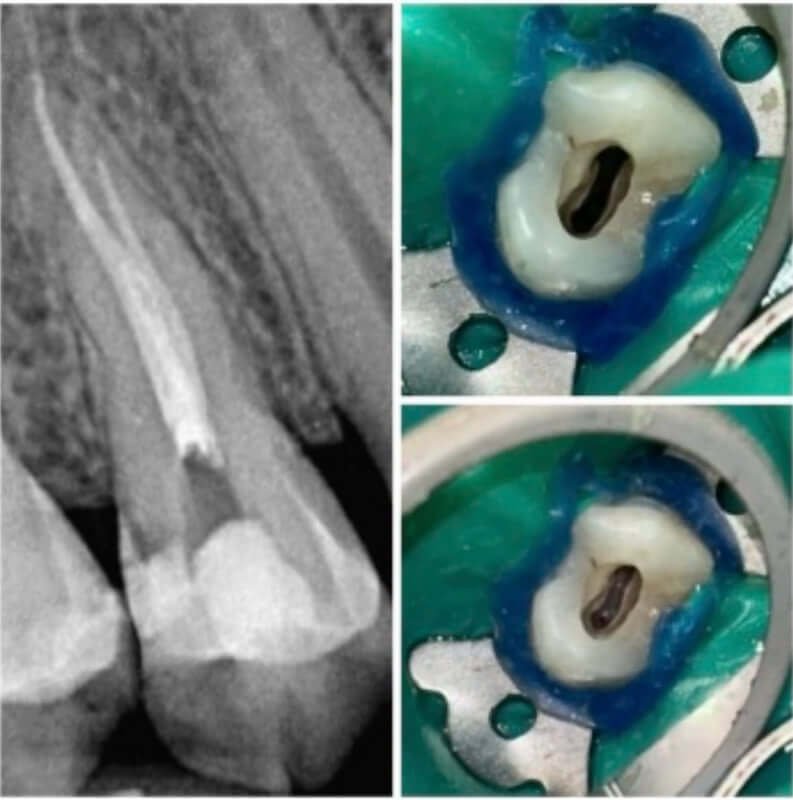

Endodonția este o ramură esențială a stomatologiei, axată pe diagnosticarea, prevenirea și tratamentul afecțiunilor pulpei dentare și a țesuturilor periapicale. Această specialitate joacă un rol crucial în salvarea dinților naturali, evitând extracțiile și menținând sănătatea orală pe termen lung. Prin tehnici avansate și echipamente de ultimă generație, endodonția asigură tratamente precise și eficiente, contribuind la redarea sănătății și funcționalității dinților într-un mod durabil și predictibil.

Utilizarea tehnicilor moderne asigură un tratament rapid, precis și confortabil pentru pacient.

Tratamentele corecte reduc riscul de infecții și complicații viitoare.